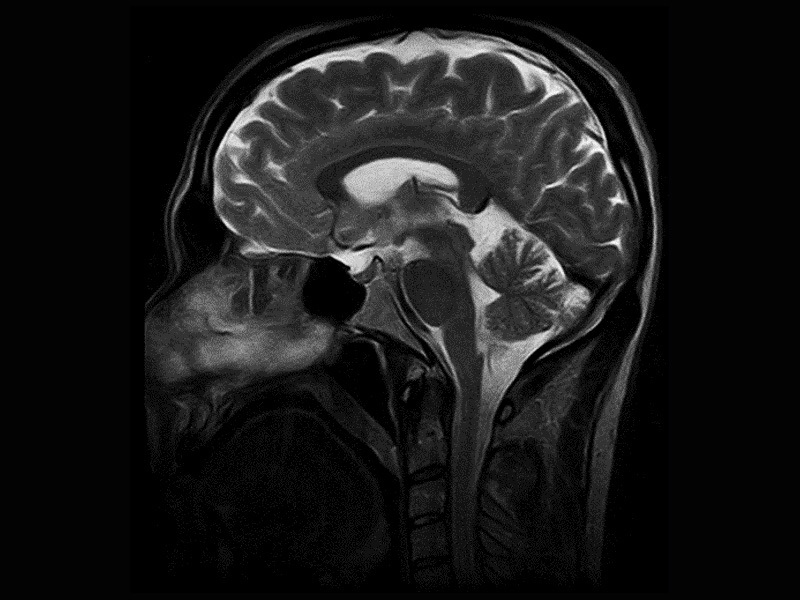

Klinické snímky